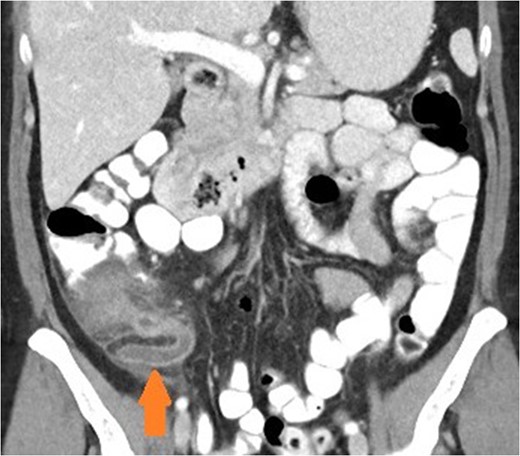

Coronal view of patient with appendicitis. Dilated and thick walled appendix (arrow).